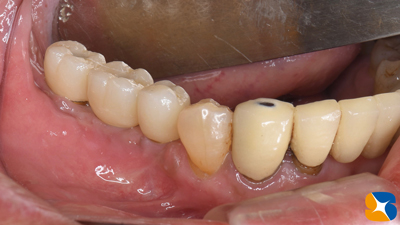

奈良 生駒 石切 インプラント 寝ながら無痛インプラント 良心価格 10年保証 再生医療 施術から2ヶ月後の型取り前の様子。当院では、必ず仮の歯を用意・装着して「噛み合わせの慣らし」を行います。